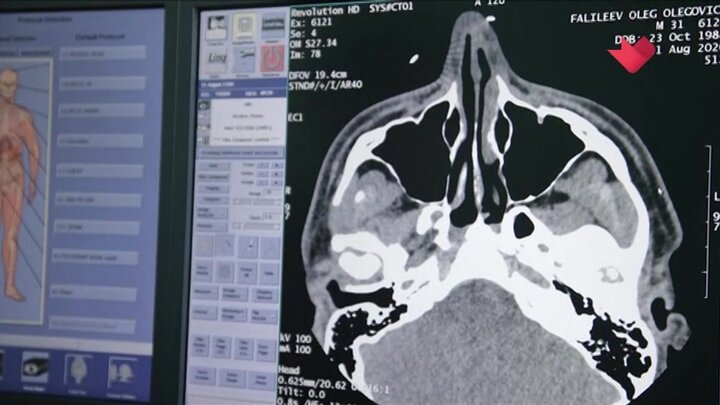

Столичные врачи-рентгенологи в июне начнут применять алгоритмы искусственного интеллекта для выявления остеопороза и признаков ишемической болезни сердца на компьютерной томографии (КТ).

Сейчас технологии в рамках московского эксперимента помогают анализировать четыре вида исследований. До конца года врачам станут доступны алгоритмы для обработки еще девяти новых направлений исследований.